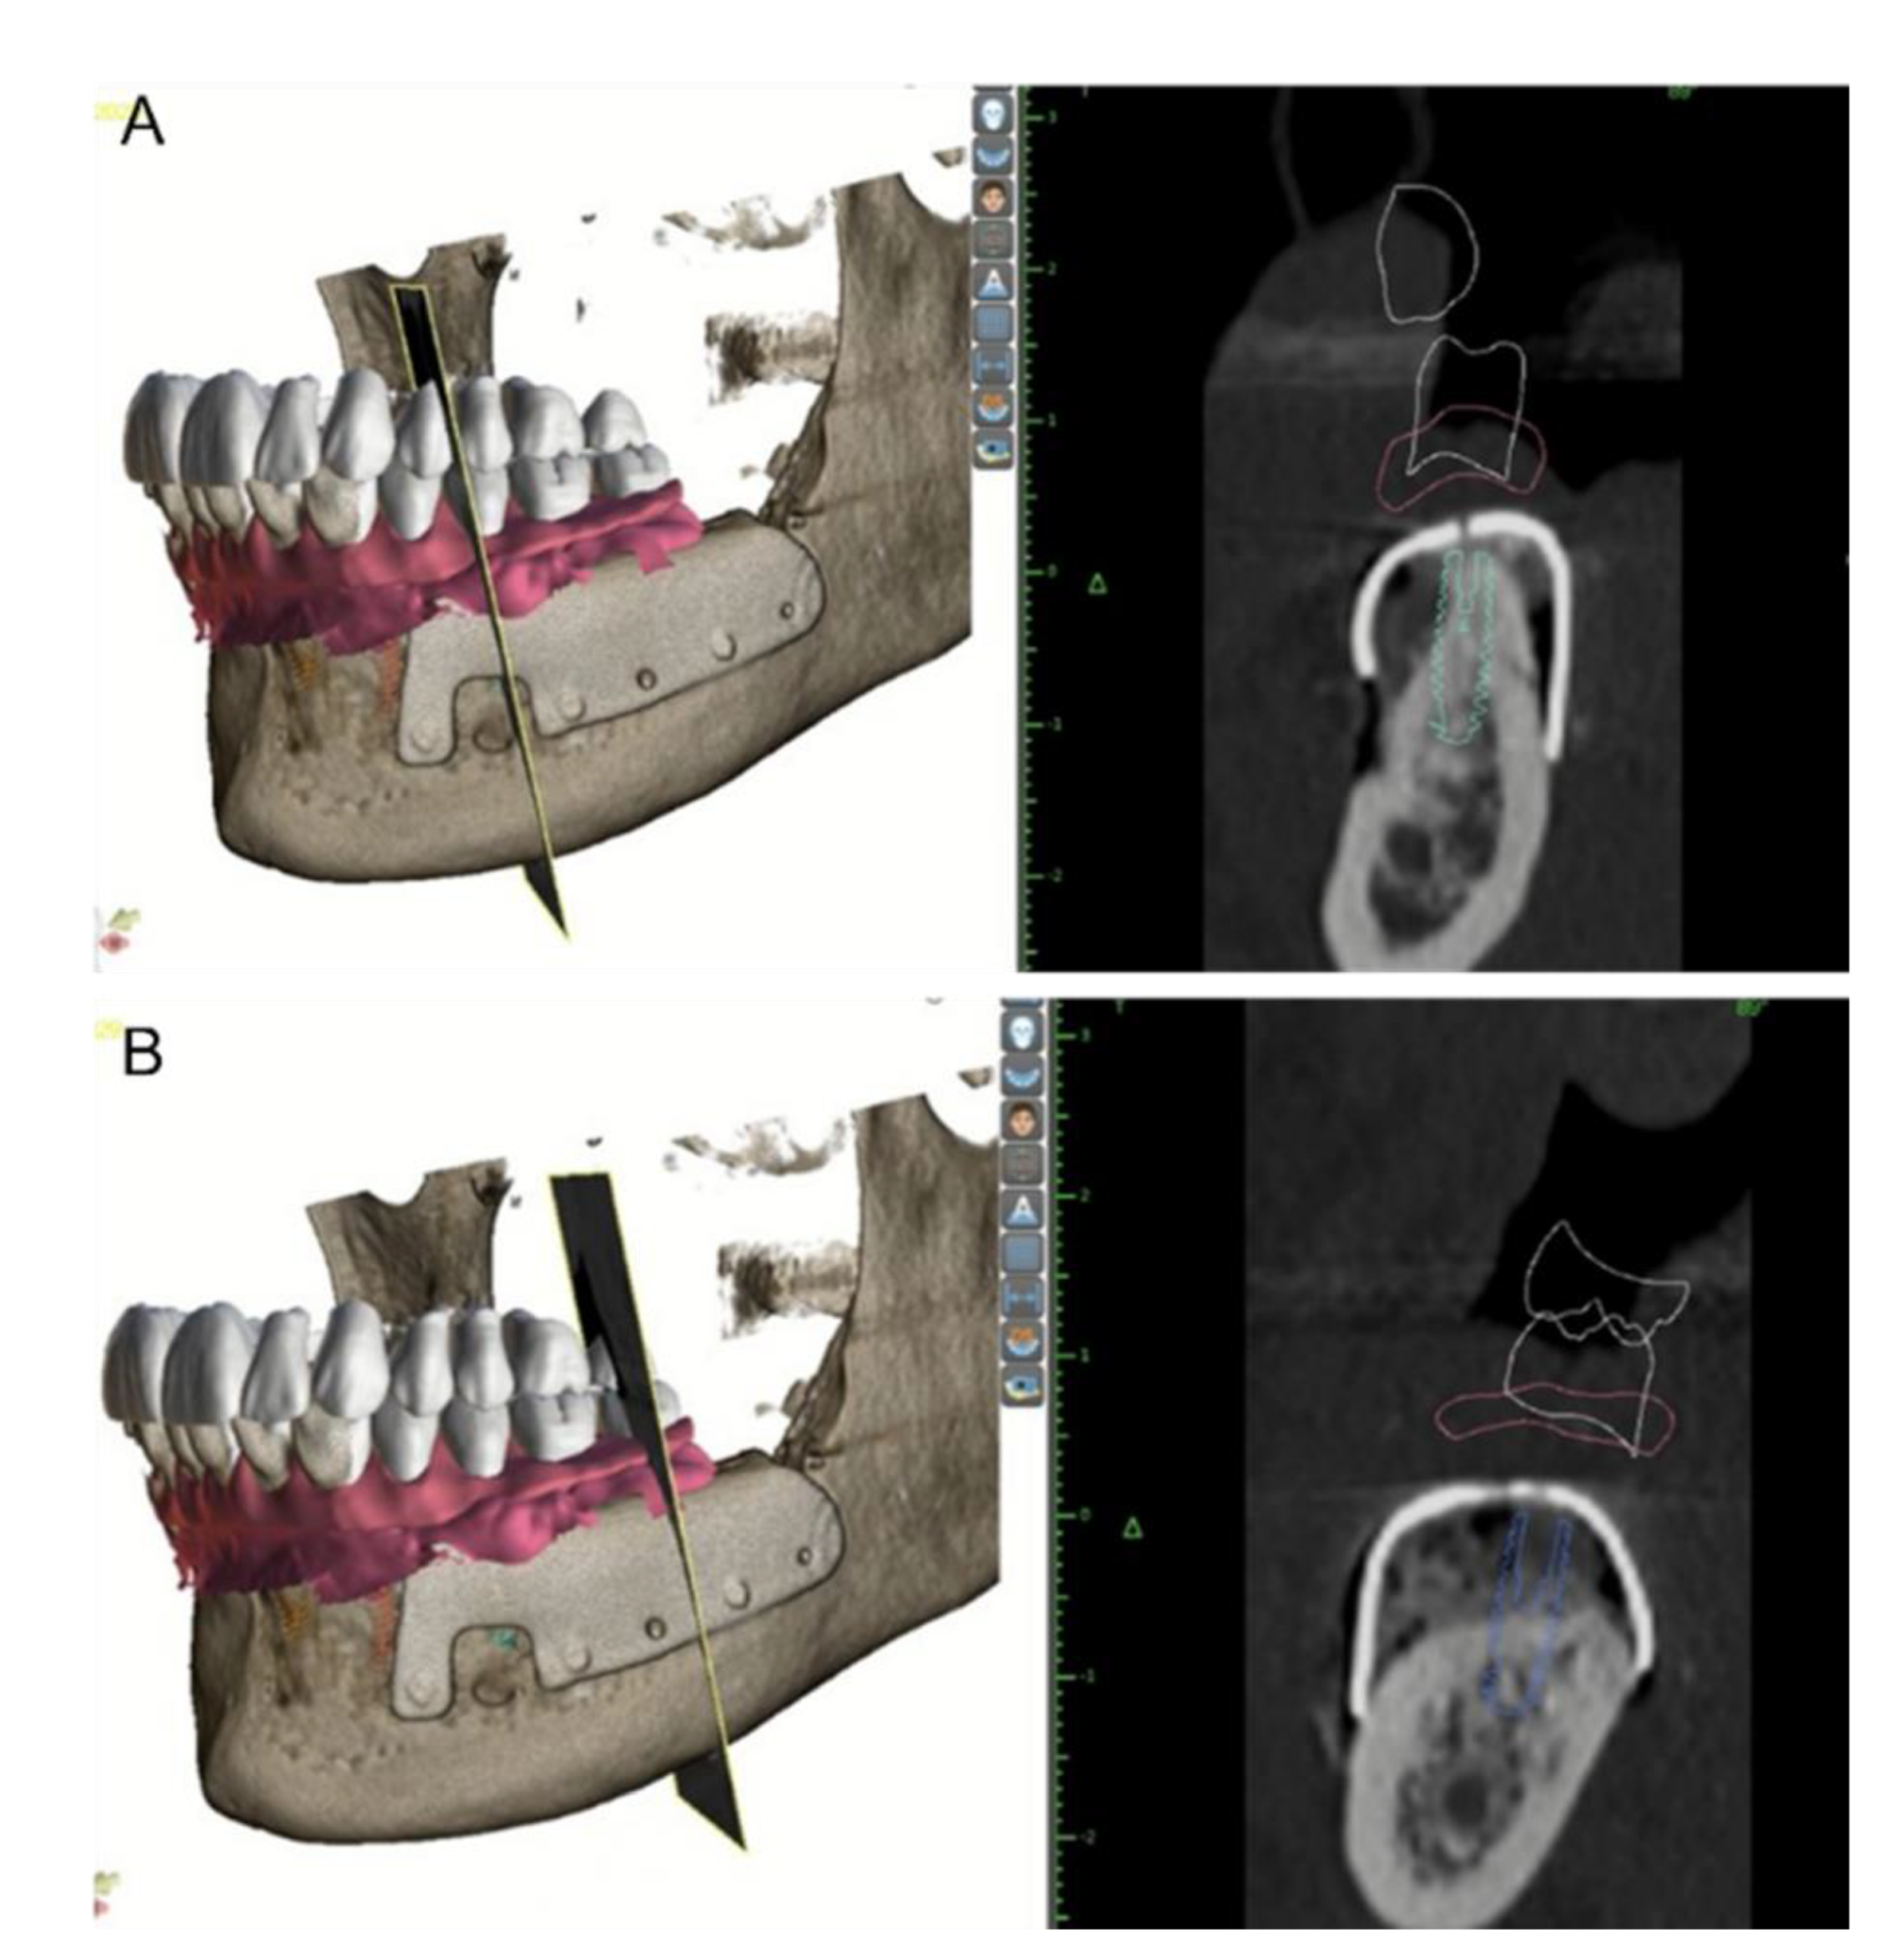

2. Materials and Methods